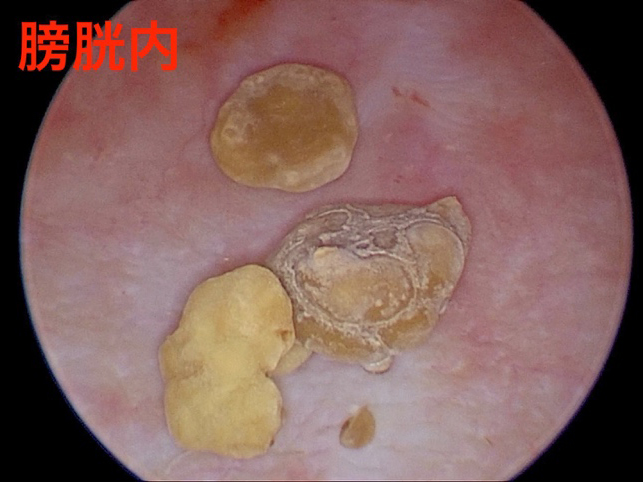

内視鏡カメラにて石の取り残しがないことを確認

取り出した結石です。全部で13個の結石を摘出しました。